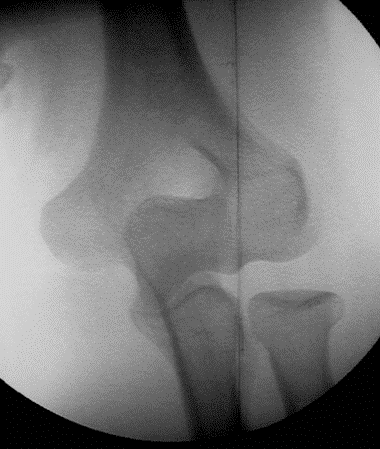

Fracture épitrochlée

Réduction au bloc et ostéosynthèse impérative.

Fracture de l’épicondyle

Dans ce cas, réduction au bloc et ostéosynthèse du fragment.